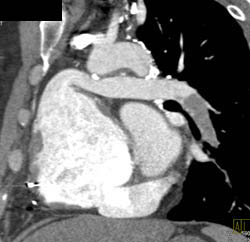

Dilated Aortic Root